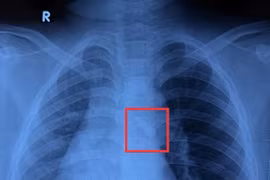

Phẫu thuật thành công lấy dị vật răng trong đường thở bé trai 10 tuổi

Chấn thương vùng hàm mặt, răng gãy hoặc rơi ra có thể bị hít vào đường thở mà không biểu hiện rầm rộ ngay từ đầu, dễ bị bỏ sót.